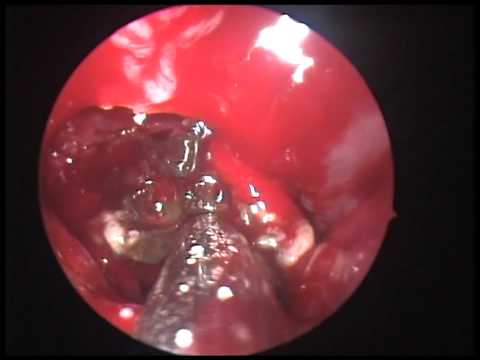

Ход операции

Эндоскопическая гайморотомия обычно выполняется при местном обезболивании, но в некоторых случаях может потребоваться общий наркоз. Перед проведением операции производится тщательное промывание носовой полости и синусов специальными антисептическими растворами. Удаление грибкового тела осуществляется с помощью эндоскопических щипцов. После удаления патологического очага гайморова пазуха повторно обрабатывается антисептическими растворами. Ход операции контролируется с помощью микрокамеры. Средняя продолжительность хирургического вмешательства составляет 20–30 минут.

Поскольку грибковое тело не проникает в слизистую оболочку гайморовой пазухи, его можно рассматривать как инородное тело. При наличии современного оборудования и опытного специалиста его успешно удаляют с помощью эндоскопического оперативного вмешательства. В настоящее время это является стандартом золотого уровня для малоинвазивной хирургии.